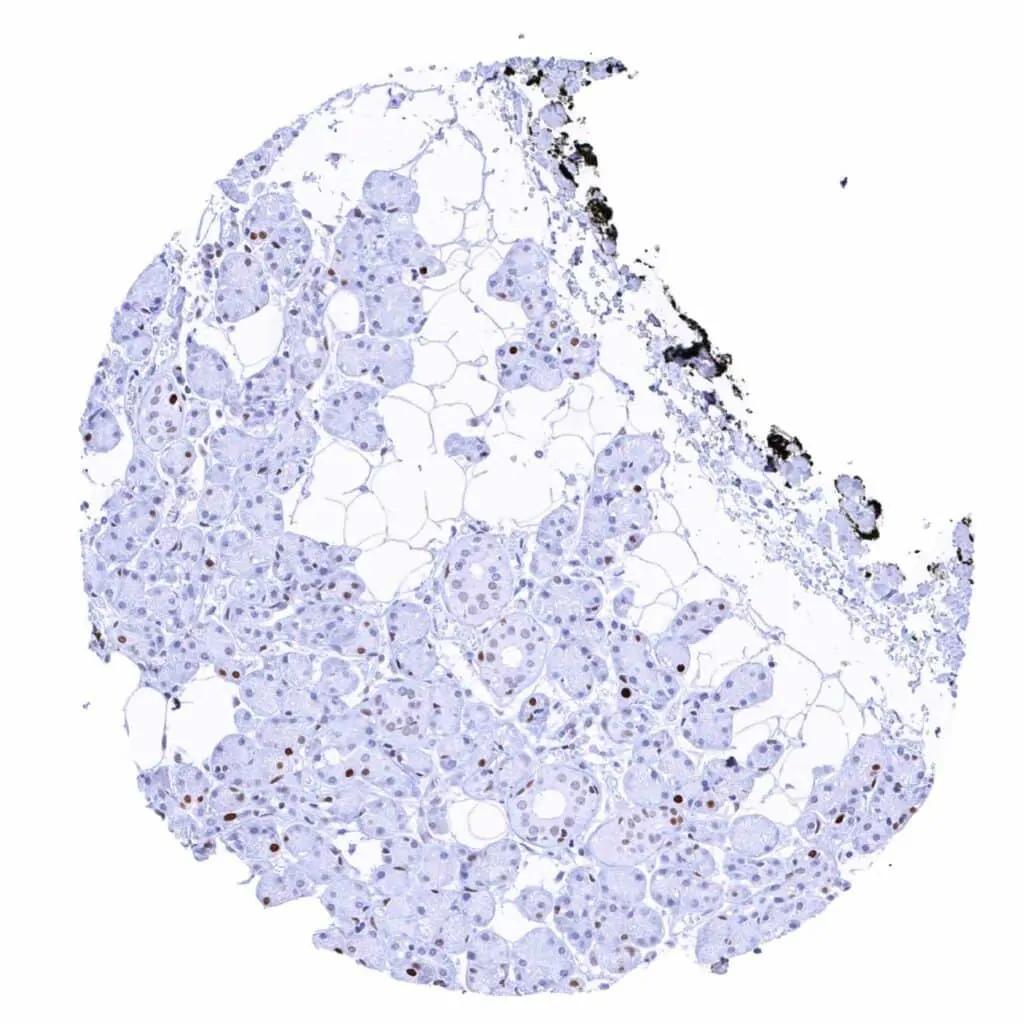

Thyroid gland – Weak to moderate MCM2 staining of a small fraction of follicular cells